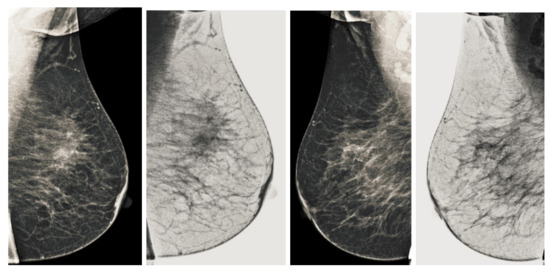

Figure 7.

Analysis of CC view of BI-RADS-1 mammogram images.

Figure 8.

Analysis of MLO view of BI-RADS-1 mammogram images.

We also measured the PSNR, the image contrast, and the EME of each category of databases, as we analyzed the image in terms of visual observation. The Table 3 shows the performance of our proposed image enhancement method. It can be seen from the Table 3 that our proposed method improved PSNR, contrast, and EME, and this also shows that our method can work on every category of BI-RADS. Because many techniques do not work on higher grade BI-RADS due to the complexity and the images are not of good quality. We obtained an average improvement in PSNR, contrast, and EME in the Table 4. For more observations, we analyzed the visual image of each category and we analyzed the CC and MLO of each category as shown in the Figure 7, Figure 8, Figure 9, Figure 10, Figure 11, Figure 12, Figure 13, Figure 14, Figure 15 and Figure 16. From the figures, every detail of image of every category can be observed, leading to better segmentation of the abnormal region. This image enhancement technique can be used as preprocessing steps for the detection of breast cancer. It is a very fast processing algorithm and it takes on 21.13 s. It gives opportunity to medical experts to analyze the mammogram images very quickly to propose the timely treatment.